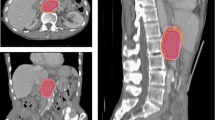

In patient 6, two observers delineated the previous RFA site (low signal intensity on delayed hepatobiliary phase on MRI) adjacent to the recurrent tumor, medially and posteriorly. There was a site of lipiodol uptake from previous TACE adjacent to the recurrent tumor. Five observers delineated the GTV including this lipiodol uptake site. The tumor in patient 6 was located in segments 2 and 3, adjacent to the pyloric portion of the stomach inferiorly, and adjacent to the heart superiorly. Additional inaccuracies may have been attributed to partial volume averaging, which enlarges with increasing slice thickness (Fig. 3).